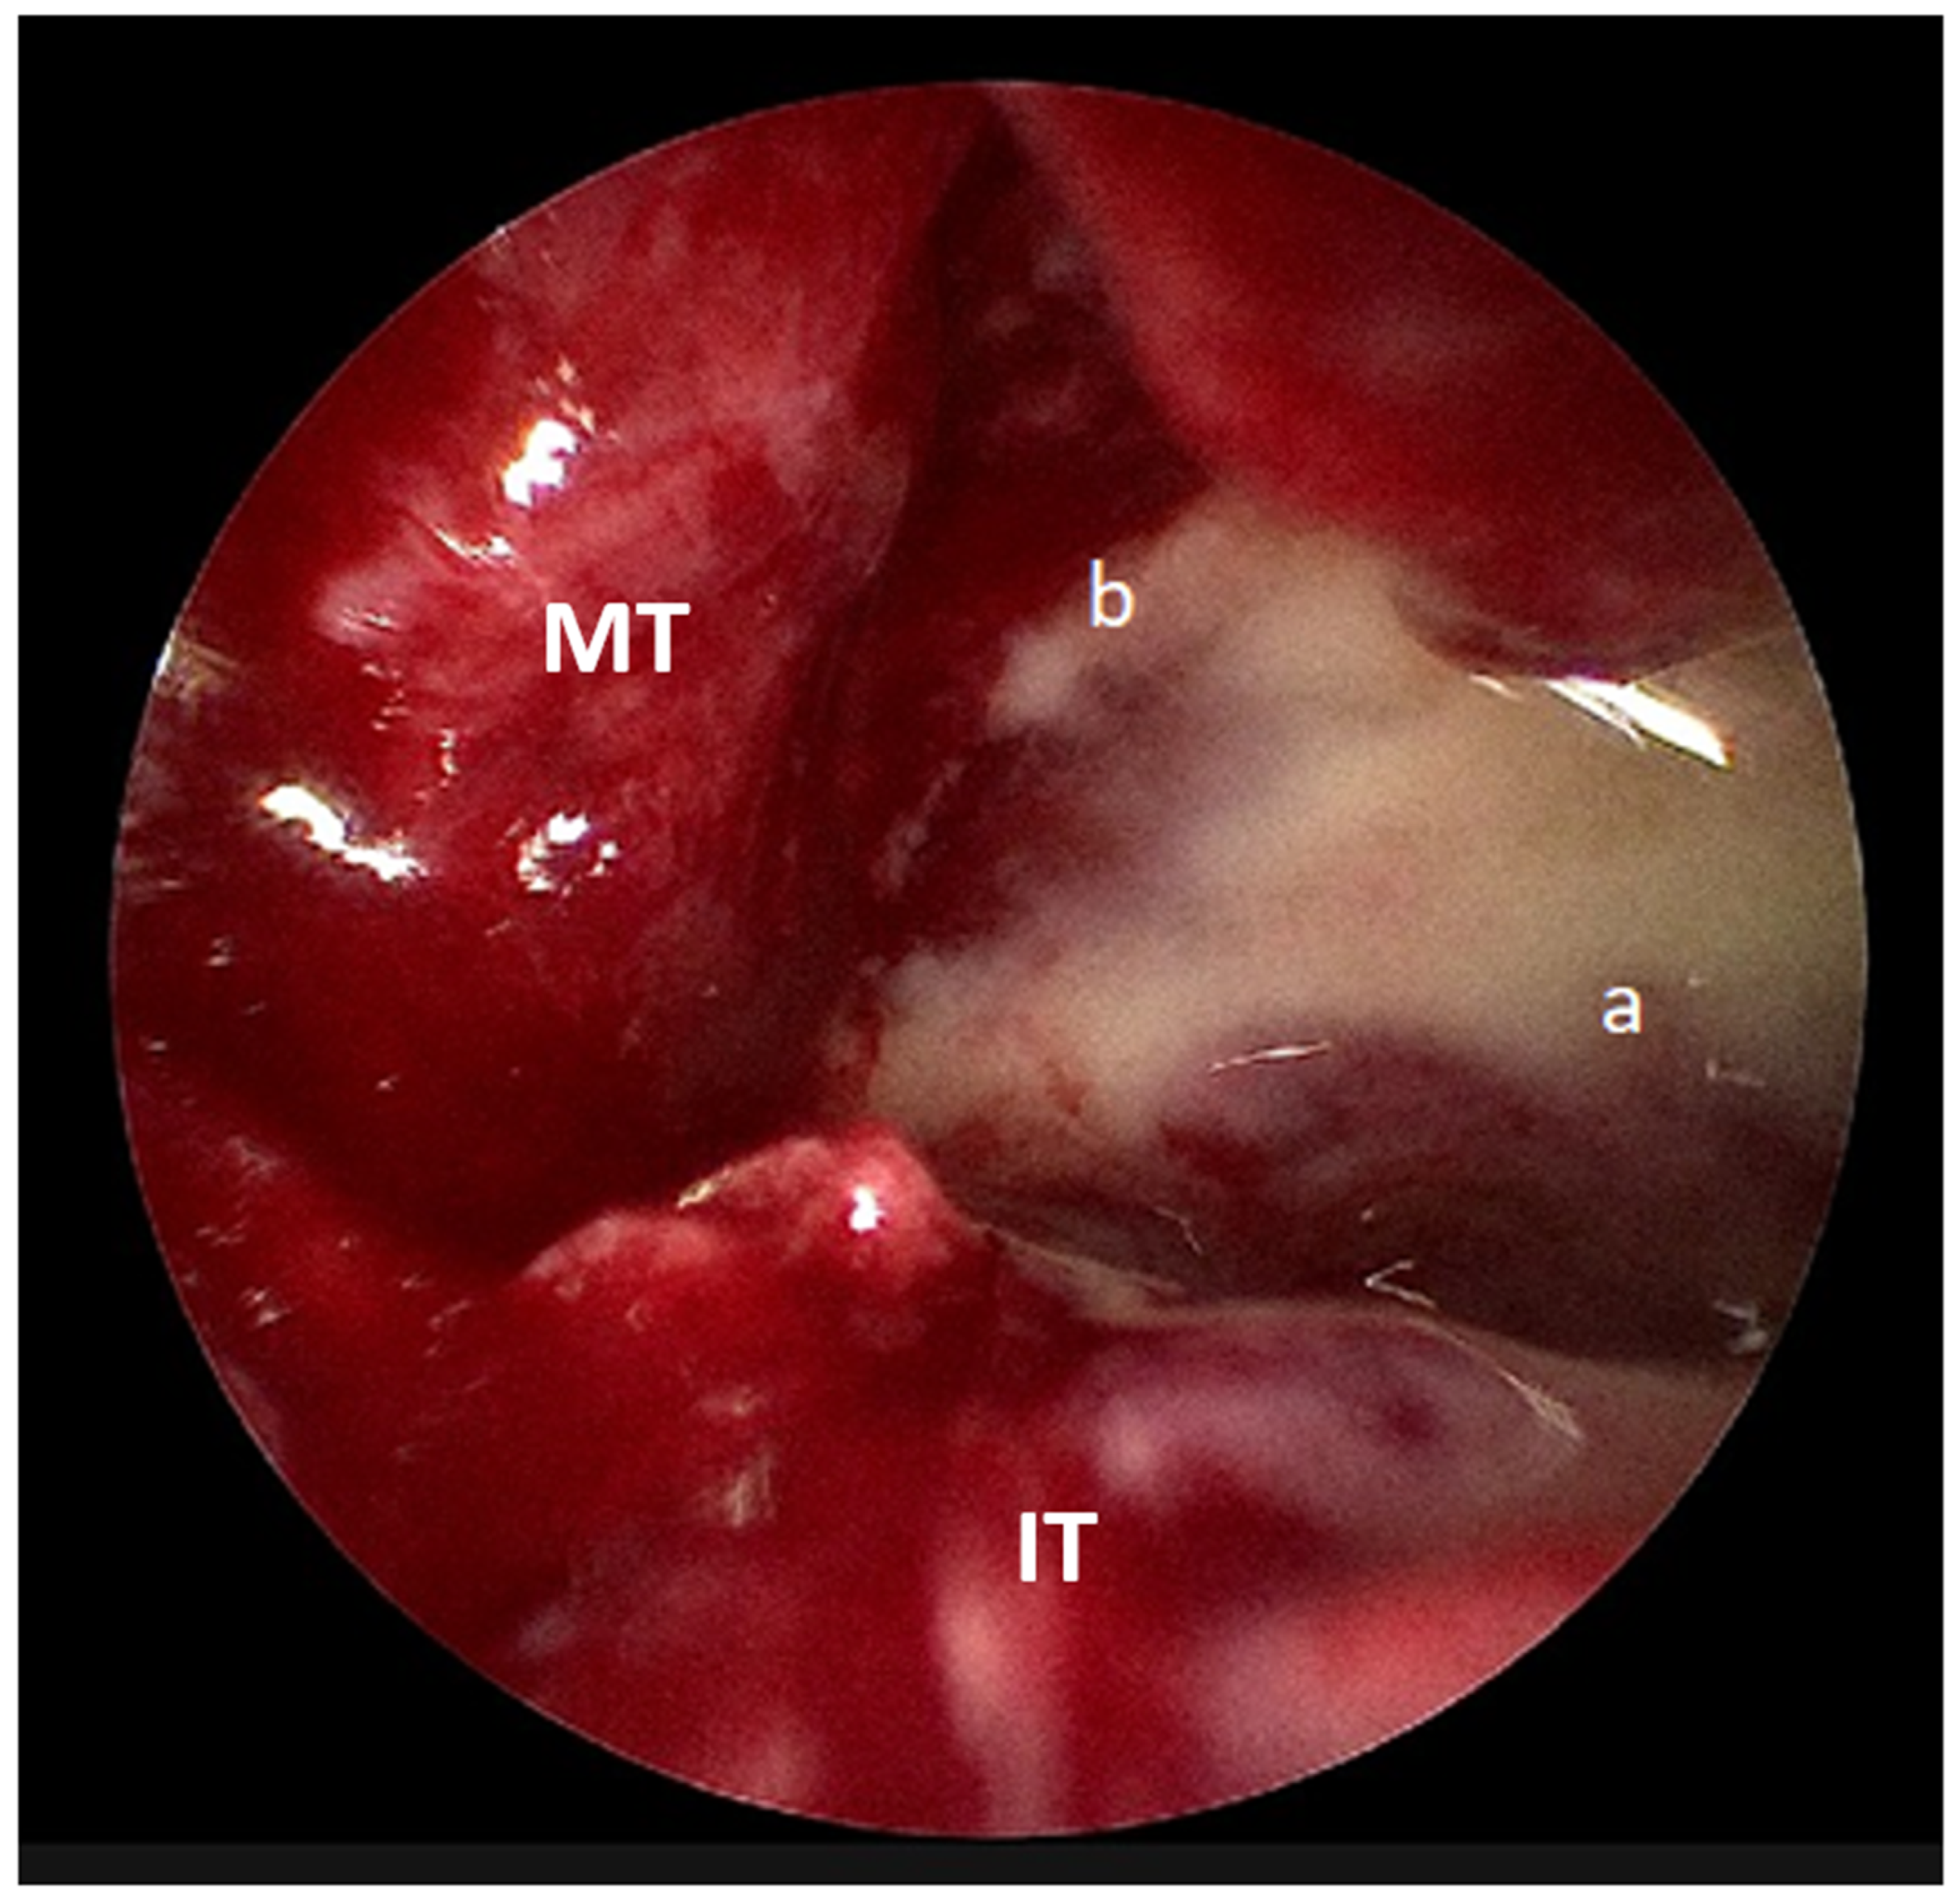

Figure 4. Intraoperative endoscopic picture showing pus draining from the (a) maxillary sinus and (b) subperiosteal region (IT: inferior turbinate, MT: middle turbinate).

The following day, he underwent endoscopic sinus surgery with drainage of subperiosteal abscess under general anesthesia. Intraoperatively, pus was observed in the left maxillary sinus and subperiosteal area (Figure 4). Postoperatively, his general condition improved; however, tissue and pus cultures obtained from the left maxillary sinus subsequently grew methicillin-resistant Staphylococcus aureus (MRSA). In response, his antibiotic regimen was adjusted to intravenous vancomycin, as recommended by the infectious disease specialist.